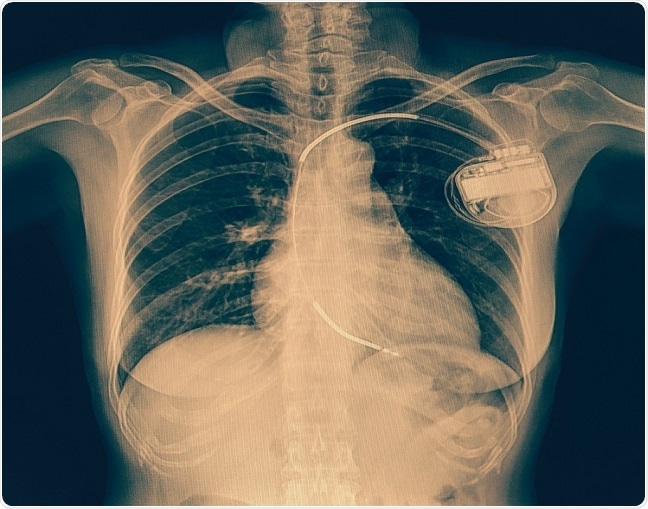

Currently, the main therapy for children at risk of sudden cardiac death is the surgical implantation of a cardioverter defibrillator. However, this involves invasive surgery and prolonged hospitalization, when in many cases, young patients only need a temporary “bridge” to help their heart. They may be waiting for a heart transplant, for example, or be recovering cardiac function after having been newly diagnosed with heart failure. In instances such as these, patients would not be good candidates for surgically implanted devices, explains Spar.

© Kasa1982/Shutterstock.com